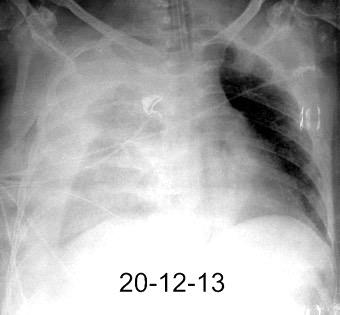

By-pass coronario 21-10-03

Marzo 2014: Perforación longitudinal distal secundaria a episodio de vómito (síndrome de Boerhaave). Derrame pleural izdo. que evoluciona a empiema.

Wang C-T et al. Tension hydropneumothorax in a Boerhaave syndrome patient: A case report . World J Emerg Med, 2021. Katabathina V et al. Nonvascular, nontraumatic mediastinal emergencies in adults:a comprehensive review of imaging findings. Radiographics. 2011.